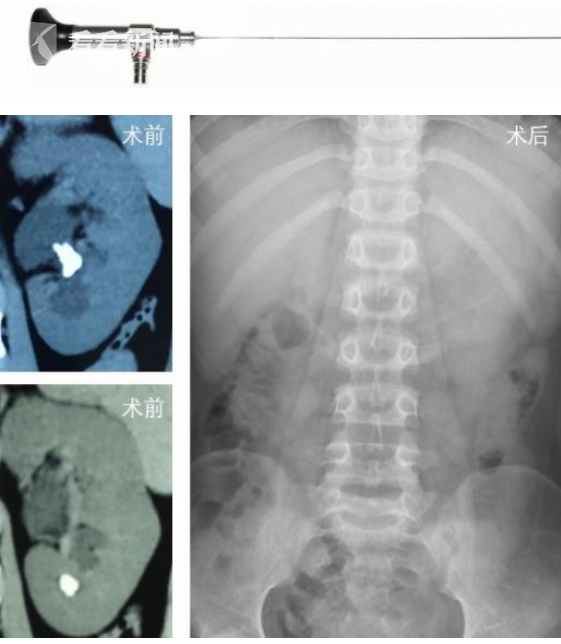

此次成功实施的UMP,全称为超细通道经皮肾镜碎石术,它通过建立皮肤和肾脏通道,将结石在肾脏内予以钬激光粉碎,再由通道引出。UMP是当前泌尿外科领域最细的内窥镜,直径仅为1mm,由于皮肾通道微小,极大降低了术中术后出血丢肾的风险,尤为适用于婴幼儿、儿童患者。

据介绍,乐乐因患复杂的左肾下盏多发结石伴下盏积水,曾多方求医无果,后经当地医院推荐来到了上海儿童医学中心。给乐乐接诊的是儿中心泌尿外科结石专业组的孙杰教授和钟量主治医师。考虑到乐乐下盏结石的位置及角度特殊,体外冲击波碎石无法达到理想效果,孙杰教授团队为患儿施行了输尿管软镜下的钬激光碎石,清除了部分结石。然而,由于下盏夹角狭小,盏颈细长,输尿管软镜无法进一步深入探查。为进一步扩大疗效,治愈疾病,经手术团队台上会诊后,果断改行UMP技术,采用双镜联合的方式,历时20分钟成功清除乐乐左肾内的所有碎石,术后复查显示无结石残留。乐乐恢复良好,第二天便顺利出院。

此次孙杰主任团队仅历时20分钟便完成了UMP手术全过程,术后无管化处理,伤口微小,完美诠释了儿科领域治疗肾脏结石的微创取石新方法,标志着我国儿科泌尿结石专业走进微创新“石”代。